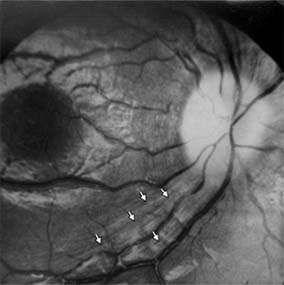

Figure 14-11

Figure 14-11: Retinal nerve fiber layer in demyelinating optic neuropathy of multiple sclerosis. The upper temporal nerve fiber bundles show multiple slit-like areas of thinning (arrows) representing retrograde axonal atrophy from subclinical disease in the optic nerve. Vision in the eye was 20/20.